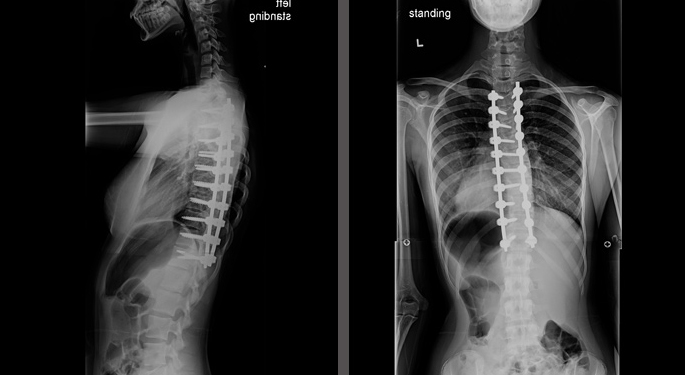

Pediatric Orthopedics and Scoliosis

Meeting the orthopedic needs of children is our specialty. We speak with our young patients of all ages and their families in a child-friendly setting. Using the most effective treatment for your child—surgical or not—we treat conditions ranging from a simple bone fracture to severe scoliosis of the spine.

Because caring for a young, growing patient requires specialized treatment, Mount Sinai’s pediatric orthopedic practice is home to not only pediatric orthopedists, but also pediatric radiologists, pediatric physical therapists, and pediatric surgeons and anesthesiologists. Our team of highly skilled doctors has a record of positive outcomes, using a range of advanced, complex surgeries as well as therapies such as bracing, casting, and injections.